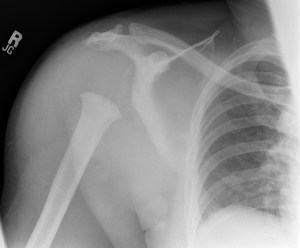

History: 40 year old patient with spinal cord injury.

This is a case of neuropathic osteoarthropathy, also known as a Charcot joint. The imaging findings are typically described as the 5 “Ds,” which include normal bone Density, joint Distension, bony Debris, cartilage Destruction, and joint Disorganization (or dislocation/deformity). Usually when seen in the shoulder it is indicative of an entity called syringomyelia, however, in this patient it was spinal cord injury.